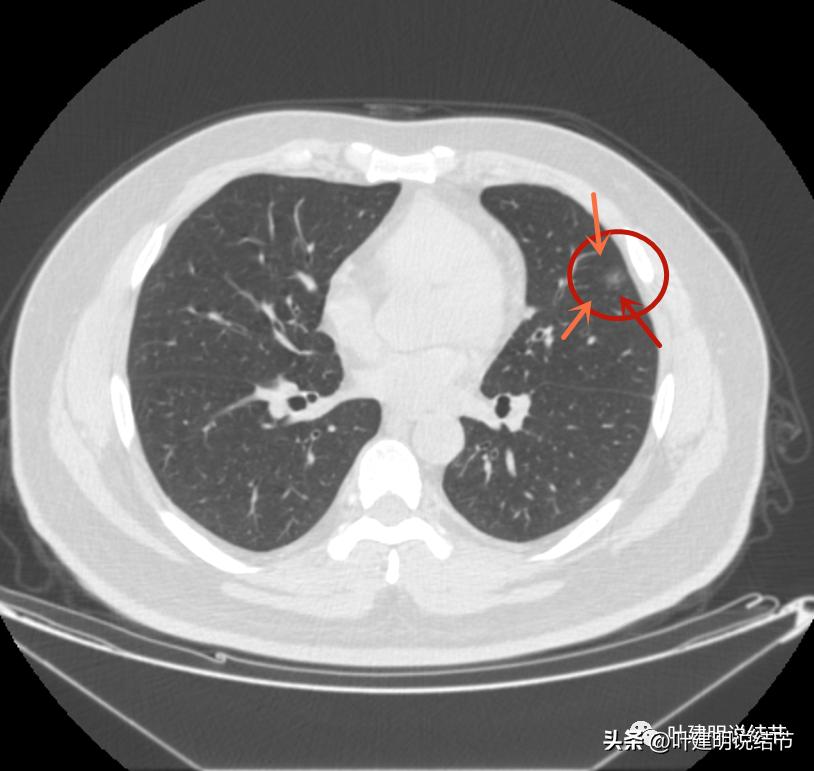

左上病灶3:混合磨玻璃结节偏实性,内部密度不均,整体轮廓清,有浅分叶,也有小血管关系密切,考虑浸润性腺癌可能性大;

边上另有病灶出现,即左上病灶3(蓝色箭头)

病灶3也有微血管进入(桔色箭头)

病灶3密度不均,轮廓清,有细毛刺样征(紫色箭头)

瘤现边界清

边上似乎有斑点状(绿色箭头),是不是卫星灶?

似乎有偏实性成分出现,密度较为杂乱

密度不均,瘤肺边界清,似乎是乱石征的影像

有偏实性成分,表面不平,边缘似乎有磨玻璃密度的成分

毛刺征(紫色箭头),微血管征(桔色箭头),实性点状成分(粉色箭头),整体轮廓较清(红色箭头)

血管弯征(桔色箭头)

血管进入

病灶3边缘部分的样子